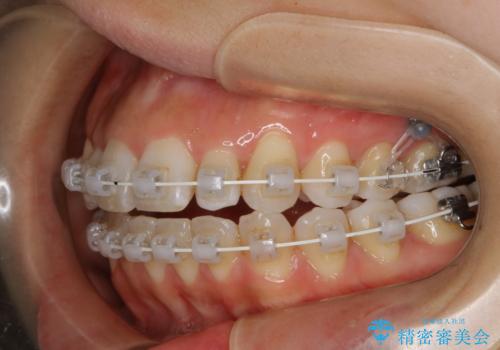

- 矯正装置

- ワイヤー矯正 審美装置

- 1年6ヶ月

- 10-30回